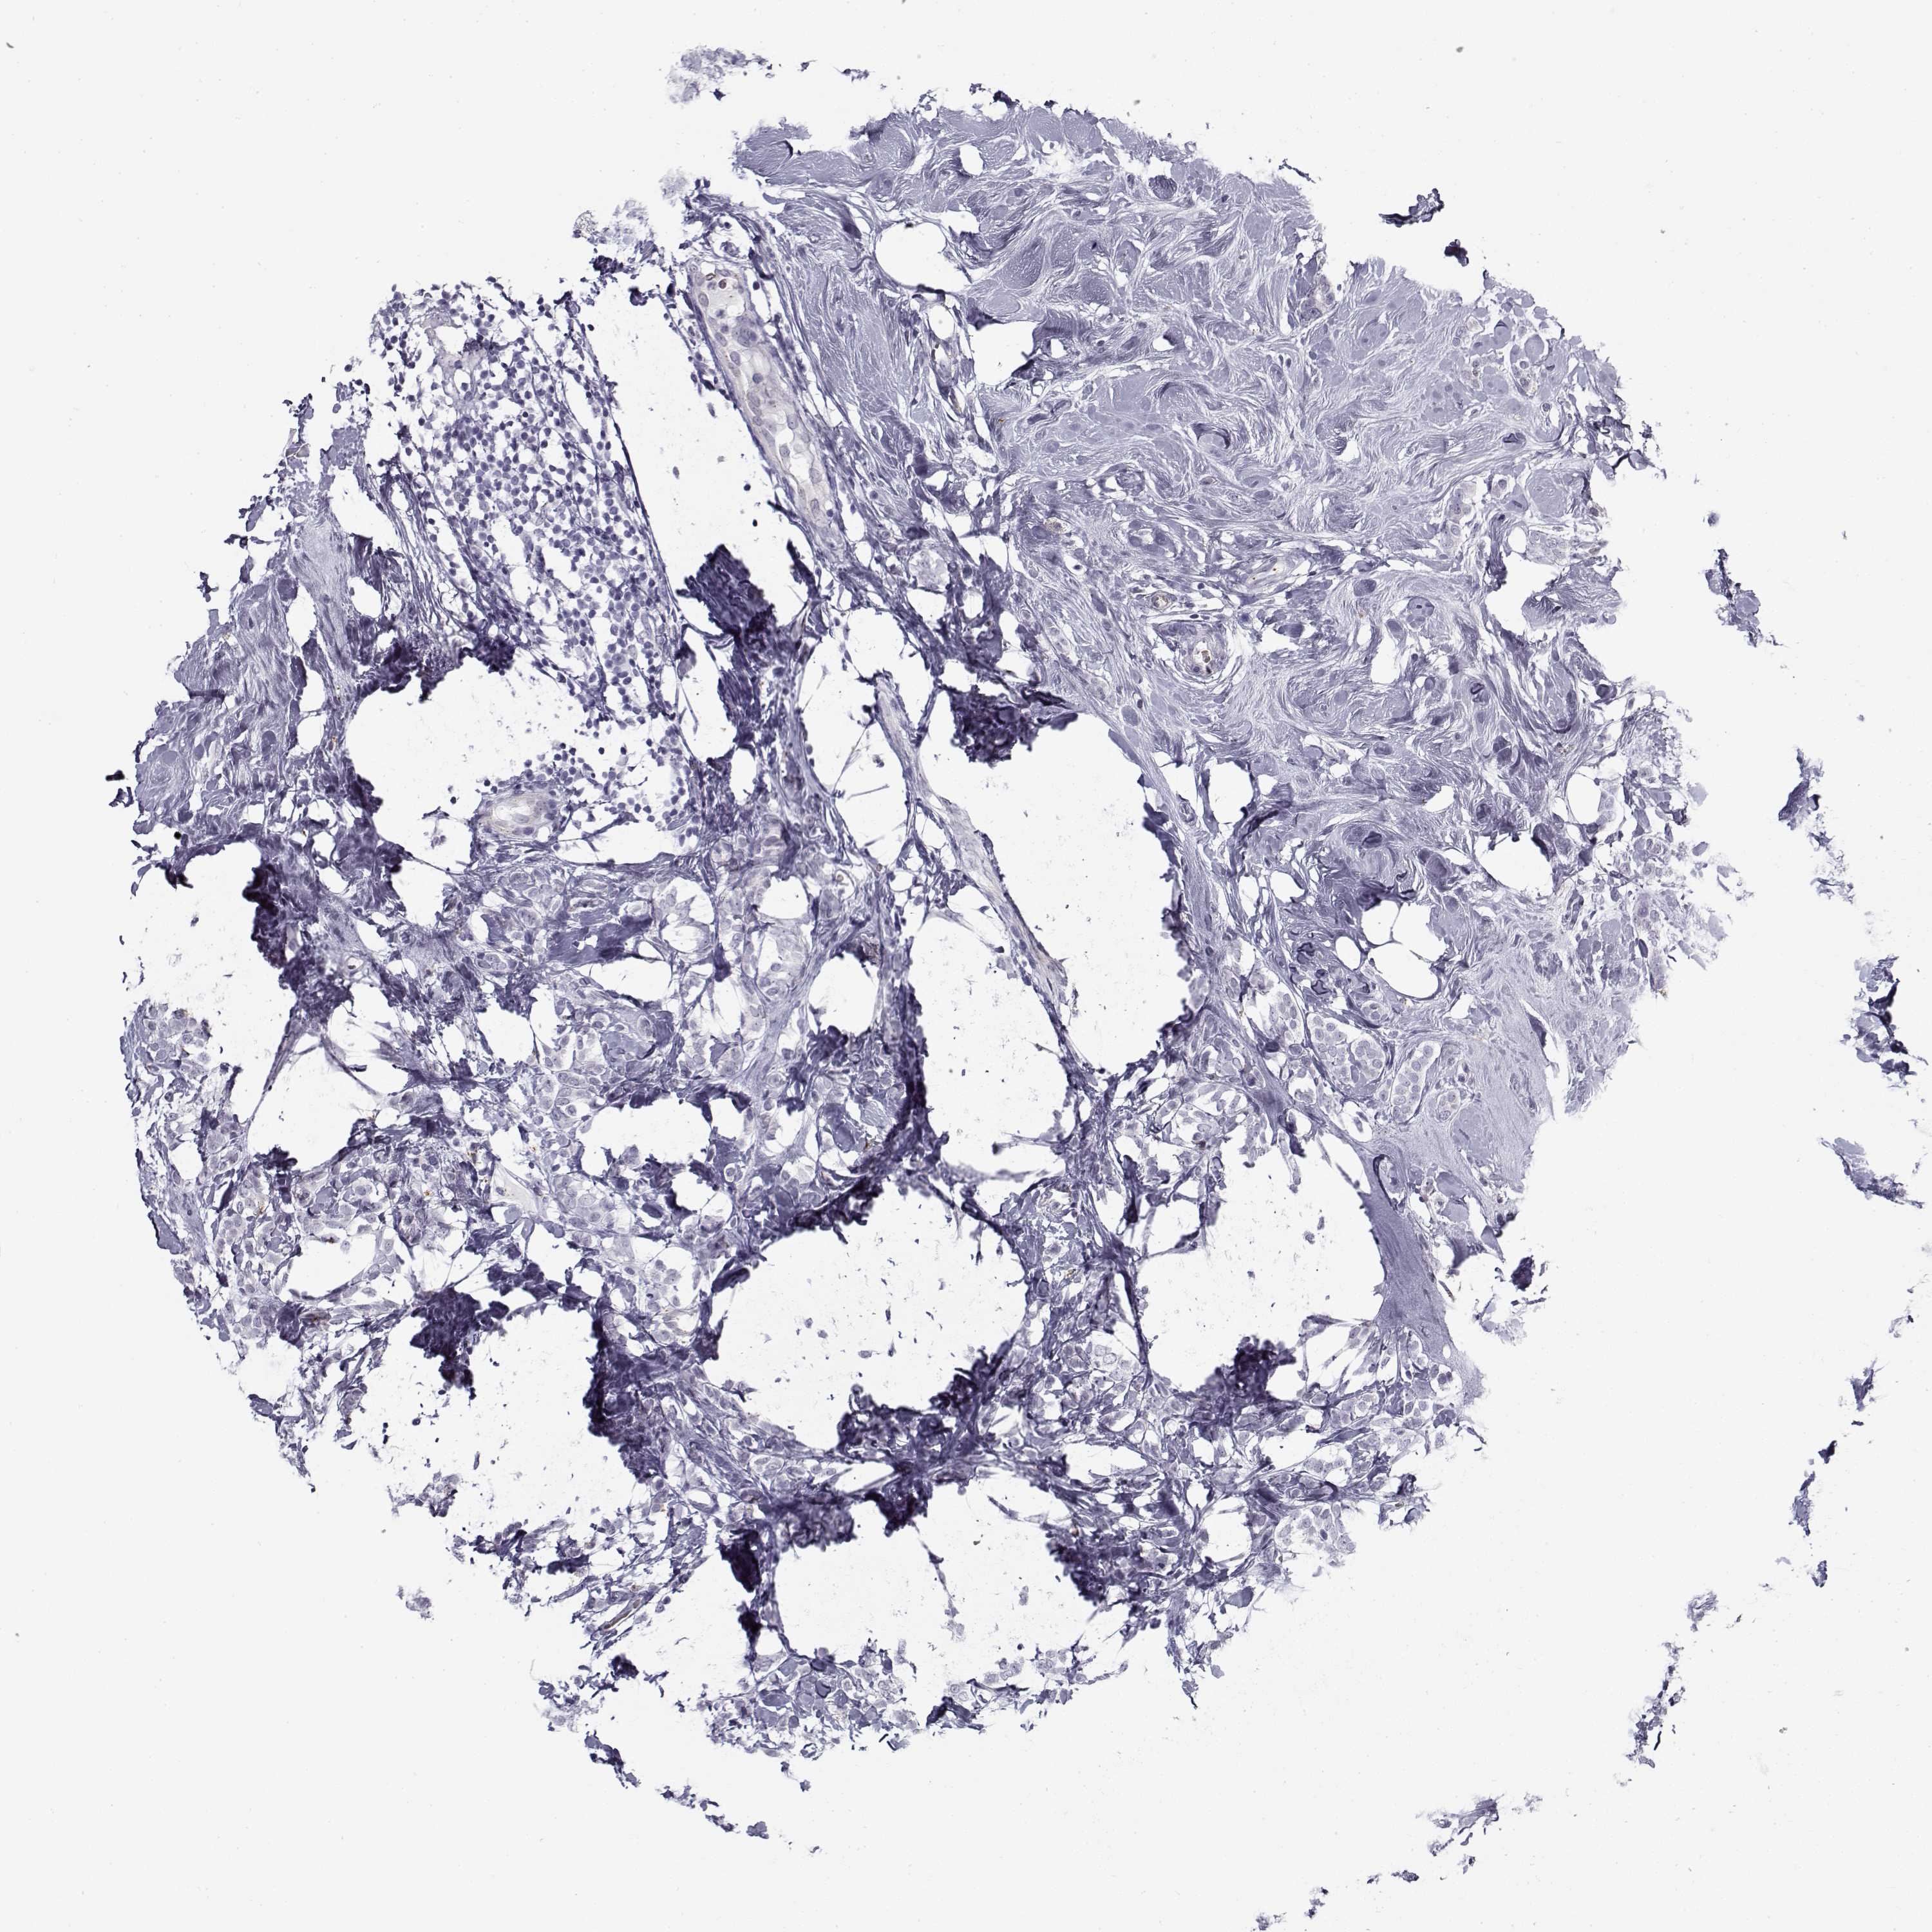

BRCA TCGA BRCA VALIDATION PROTEIN EXPRESSION

Breast cancer

Human cancer